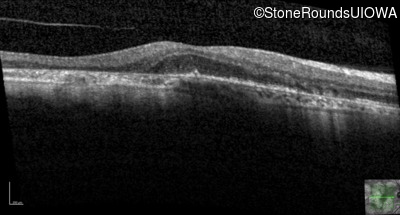

Age at visit: 51 years

This 51 year old woman first experienced some abnormality in her distance vision when she was 27 years old. She feels that her vision has been stable since that time.